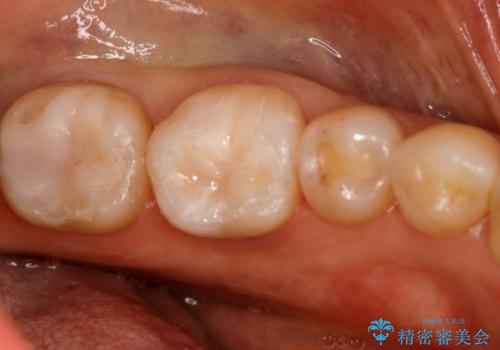

左下奥歯が腫れて痛い フルジルコニアクラウン

- 左下大臼歯の歯肉に腫れと痛みが繰り返し起こっているので治療を希望し来院された患者様です。

既に治療されている歯でしたが根尖部に病巣が確認出来たので、精密根管治療とクラウンの再治療が必要と判断されました。

精密根管治療を行なったことで病巣は消失し、腫れや痛みは再発することなく経過は良好です。

被せ物はフルジルコニアクラウンを選択されました。